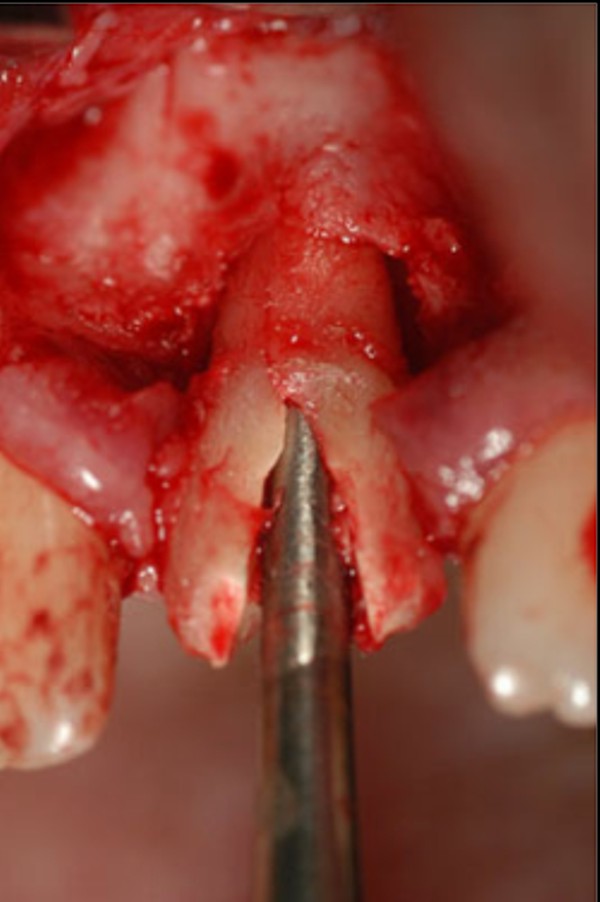

Las extracciones dentarias o EXODONCIAS, son habitualmente realizadas mediante la utilización de instrumentos denominados FÓRCEPS, los que instalados en el cuello de la pieza dentaria a extraer, son movidos de manera oscilante en el eje del diente, lográndose después de un corto período de tiempo, quitar al mismo de la cavidad ósea que lo aloja, en una operación que se denomina LUXACIÓN o AVULSIÓN. FÓRCEPS EN BOCA Esta AVULSIÓN, se produce debido a que el hueso es elástico. Sin embargo , gran parte de las veces esa elasticidad no es suficiente y se parte o rompe la «corteza ósea» que rodea al diente, en su región más cercana a la «zona cortante» del mismo.Esa ruptura o fractura, es favorecida por el uso de los Fórceps, dado que sus «mordientes» se sitúan muy cerca de del hueso. .FÓRCEPS ROMPIENDO LA TABLA TABLA ROTA La idea de crear un instrumento que impida dicha fractura, se basa en la certeza de que cuanto más adentro del diente, y cuanto más cerca de la punta del diente, se efectúe la fuerza de AVULSIÓN, menos posibilidades de fractura existirán por una simple cuestión de física básica: CUANTO MÁS LARGO SEA EL BRAZO DE POTENCIA DE UNA PALANCA, MENOS ACCIÓN TENDRA EL BRAZO DE RESISTENCIA….POR LO TANTO SERÁ NECESARIA MENOS POTENCIA PARA VENCER LA RESISTENCIA… O SEA, CON MOVIMIENTOS MAS DELICADOS , LOGRAREMOS EL MISMO EFECTO. ESQUEMA DE DIENTE MOSTRANDO LA ACCIÓN DE LAS FUERZAS DE UN FÓRCEPS. ESQUEMA DE DIENTE MOSTRANDO LA ACCIÓN DE FUERZAS DE UN AIDA Cuando la especialidad IMPLANTOLOGÍA, no se había desarrollado tal como ahora la conocemos, la fractura de esa «corteza ósea» denominada TABLA EXTERNA O INTERNA del PROCESO ALVEOLAR, carecía de importancia ya que la cicatrización se produce irremediablemente en ausencia de infecciones Sin embargo, a la luz de los conocimientos actuales, la preservación de dichas TABLAS, son de capital importancia para la realización de un IMPLANTE INMEDIATO(Implante colocado en el mismo acto quirúrgico que la extracción), y para el logro de su INTEGRACIÓN Y ESTÉTICA futura. Es por eso que exponemos ante las autoridades competentes, la idea de patentar un instrumento como el que denomino: AVULSIONADOR INTRADENTARIO ATRAUMÁTICO …cuyas características principales son: MATERIAL: ACERO QUIRÚRGICO 316 LONGITUD TOTAL:13 mm PUNTA ACTIVA: 6 mm FORMA DE PUNTA ACTIVA: HELICOIDAL DECRECIENTE DOS GROSORES DE PUNTA. INSTRUMENTO AD HOC Por acción de las espiras , el instrumento se fija en las paredes del canal dentario, produciendo un anclaje que permite la AVULSIÓN. CRESTA ÓSEA COMPLETAMENTE CONSERVADA